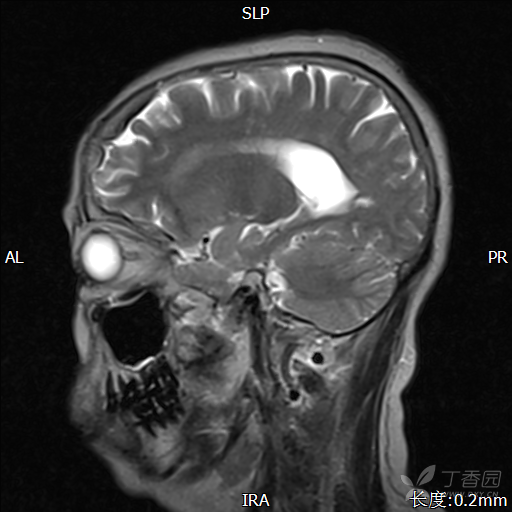

鞍区,蝶窦占位,女,65岁,左侧眼睑下垂,发现占位2年余.